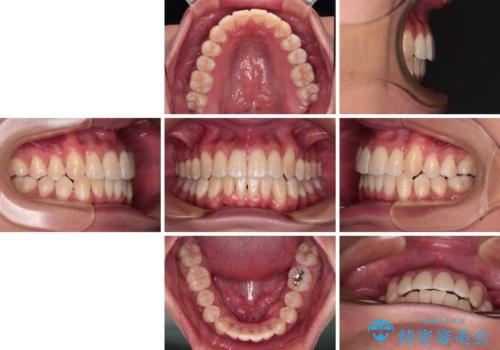

- 1年4ヶ月

- 八重歯と飛び出している前歯を気にして来院された患者様です。

歯列としてはインビザラインでもワイヤー矯正でも対応できるものでしたが、上顎の八重歯や下顎小臼歯の捻転といったインビザラインでは時間のかかってしまう歯列不正が認められたため、補助装置やワイヤー矯正を治療当初に使用することで、インビザラインによる治療をスムーズに行えるように計画しました。